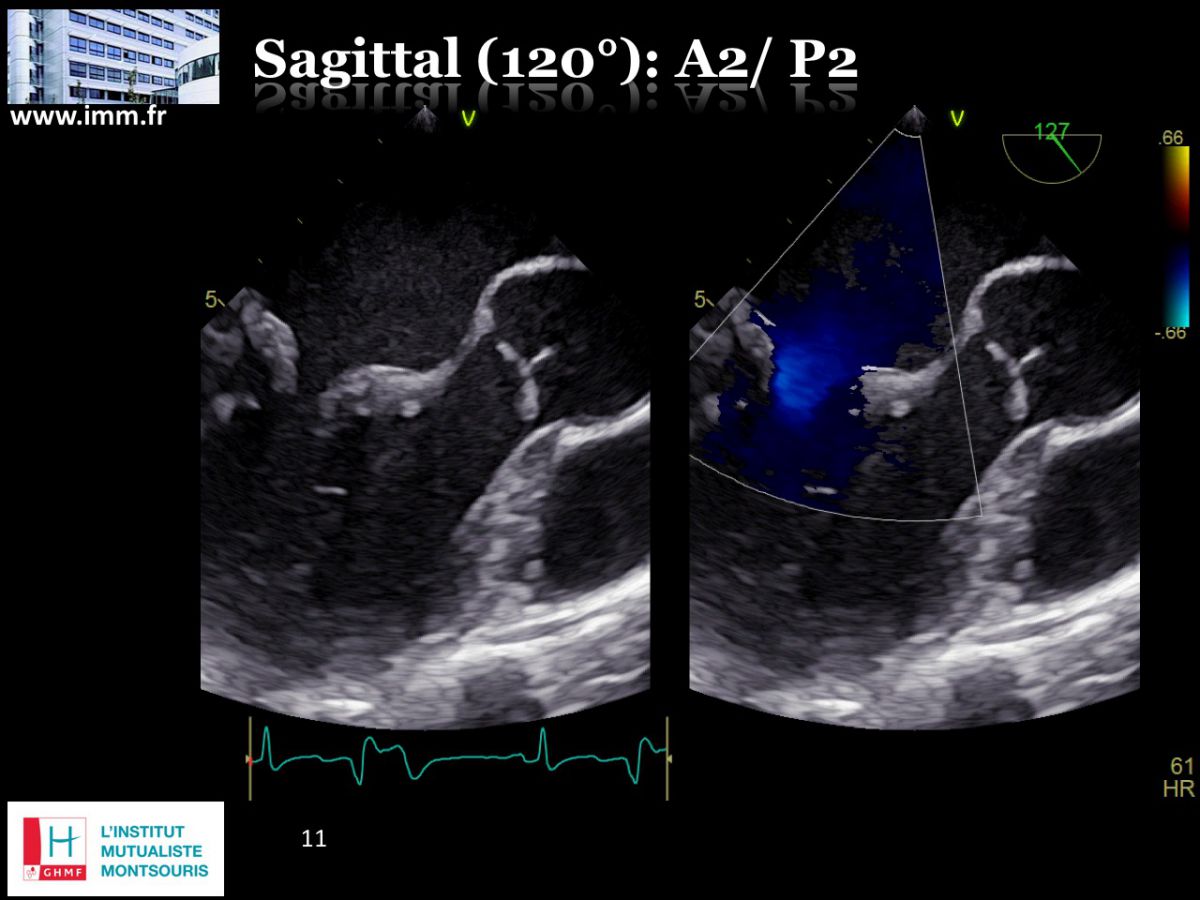

Plastie mitrale vidéo : Duo écho-chirurgical